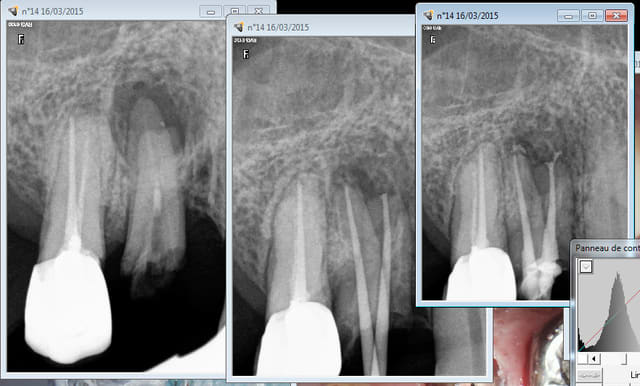

Oui, des douleurs diffuses par exemple. Ca m'a désolé de faire les endos, impossible de savoir laquelle de ces dents abrasées était responsable.

Je suis quelqu'un d'extrèmement conservateur, la preuve :

Capture d e cran 2015 03 16 20.02 - Eugenol

Capture d e cran 2015 03 16 20.03 - Eugenol

tu as obtenu cette cicatrisation osseuse en combien de temps?

> tu as obtenu cette cicatrisation osseuse en combien de temps?

20 mn, question d'angle de prise de radio. -)))))

quel con je suis, comme quoi on peut tout faire dire au radio

Elles sont toutes à la meme date et pas retouchées hein !

Ce qui en dit long sur la fiabilité du diagnostic en 2D.